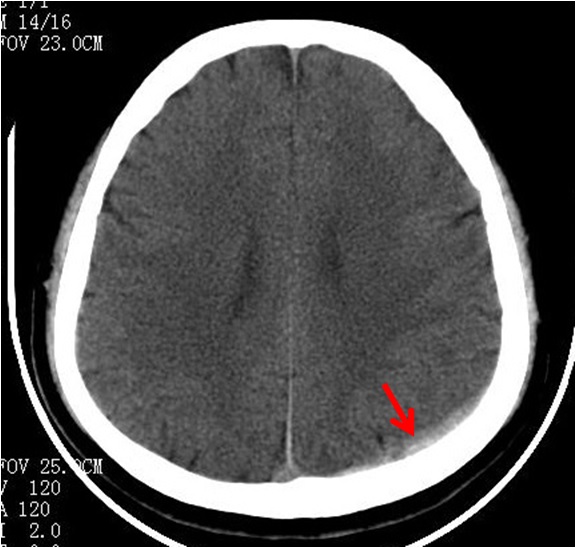

迟发性外伤性颅内血肿指伤后首次CT检查时无血肿,而在以后的CT检查中发现了血肿,或在原无血肿的部位发现了新的血肿,此种现象可见于各种外伤性颅内血肿。可能是外伤时血管受损,但尚未全层破裂,因而CT检查未见血肿;伤后由于损伤所致的局部二氧化碳蓄积,酶的副产物释放以及脑血管痉挛等因素,使得原已不健全的血管壁发生破裂而出血,形成迟发性血肿。表现为伤后经历一段病情稳定期后,出现进行性意识障碍加重等颅内压增高的表现,确诊须依靠多次CT检查的对比。迟发性血肿常见于伤后24h内,可发生在脑内、硬脑膜下或硬脑膜外,以迟发性脑内血肿较多见。